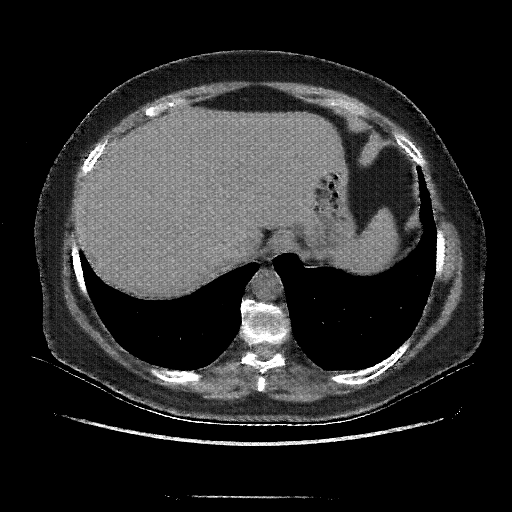

Original VENOUS CT scan

No window - Raw intensity values

Lung window (WL -600, WW 1500 β†’ Low βˆ’1350, High +150)